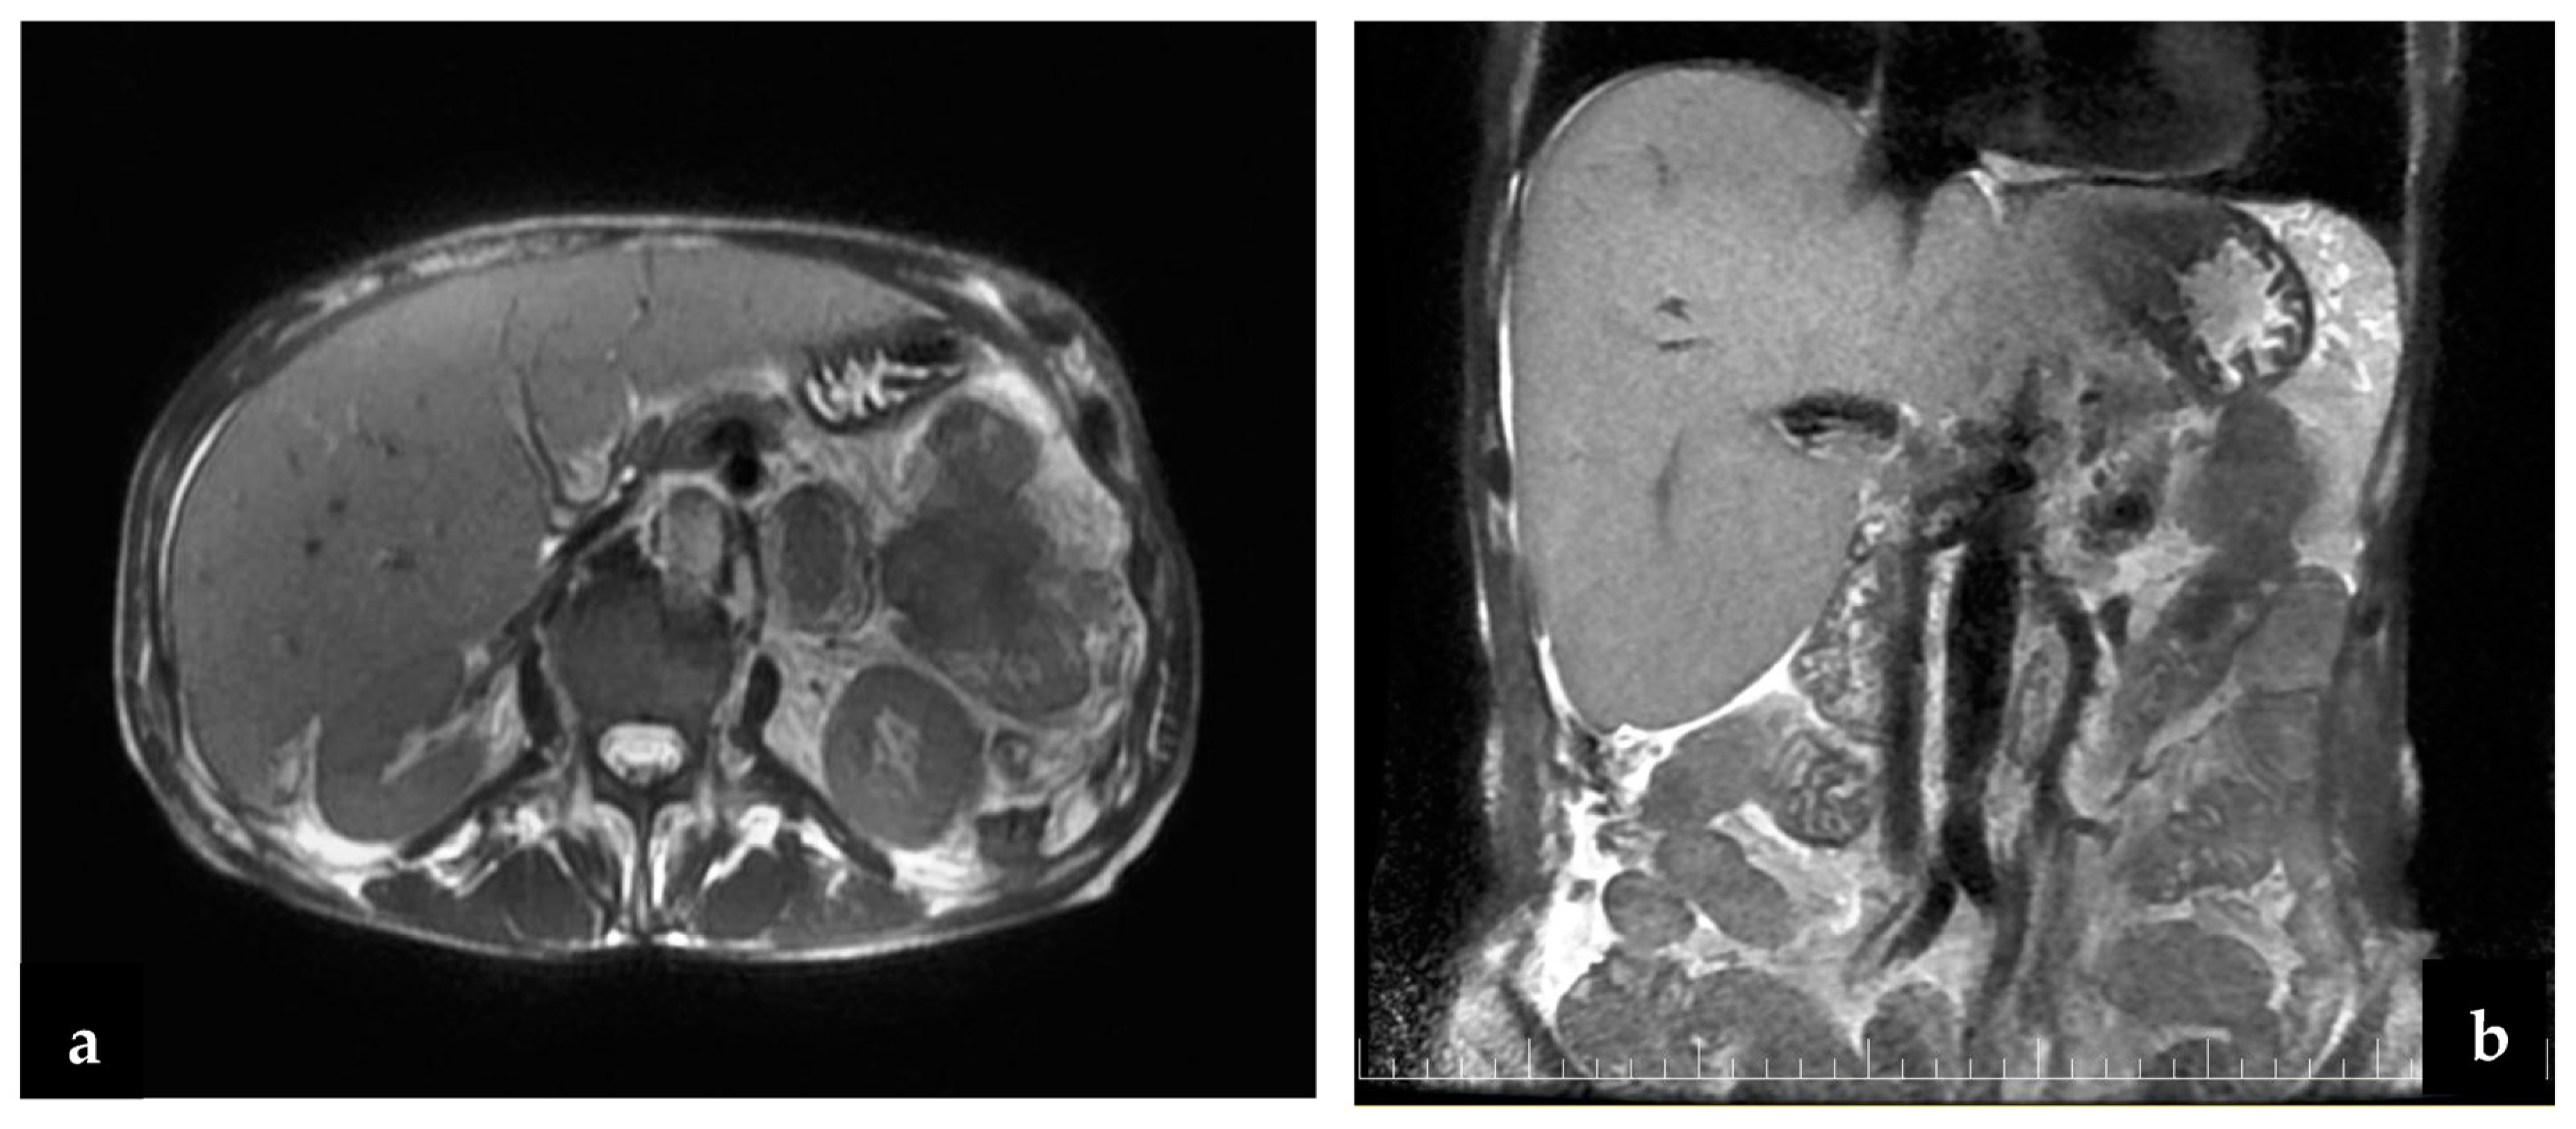

Figure 5.

(a,b) Abdominal MRI: the tumor includes the first jejunum loop and the transverse colon and invades the gastric wall.